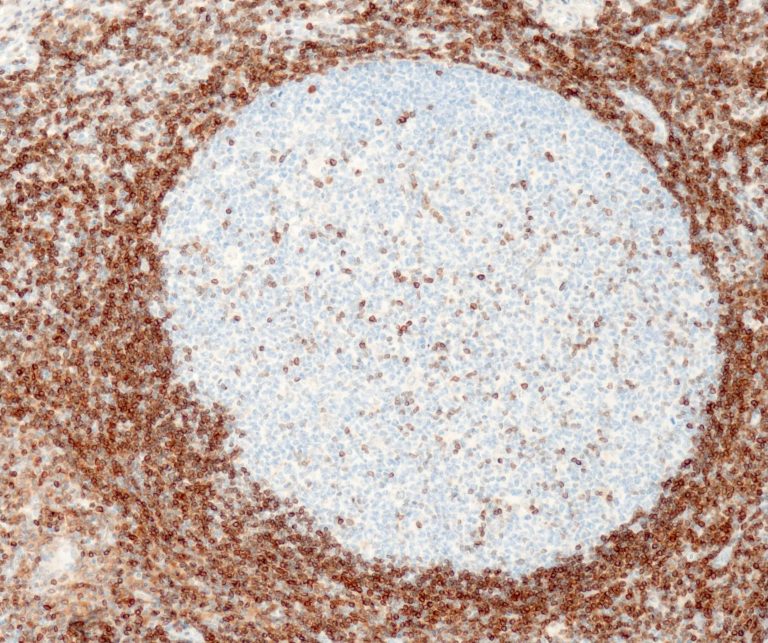

Hematopathology